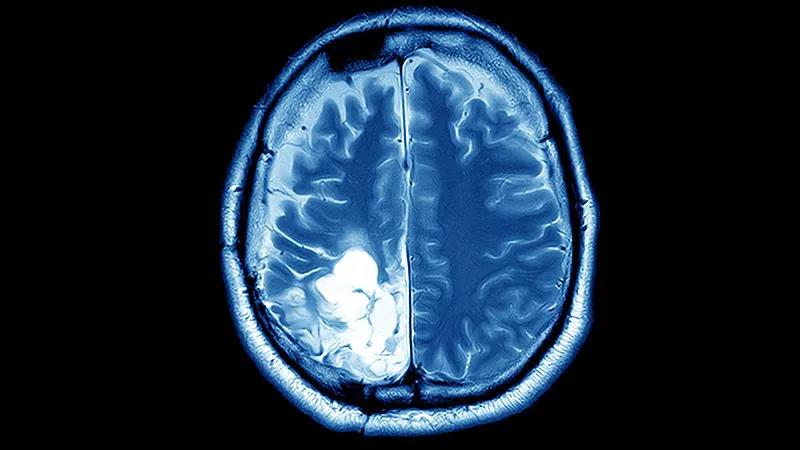

新組合療法治療乳腺癌腦轉(zhuǎn)移,生存率達(dá)75%!

然而,腦轉(zhuǎn)移的發(fā)生率也水漲船高,可達(dá)55%。當(dāng)乳腺癌細(xì)胞擴(kuò)散到大腦時,患者的生存期將大大縮短,通常只有6個月。目前仍缺乏針對乳腺癌腦轉(zhuǎn)移的靶向療法。

近日,美國西北大學(xué)一項(xiàng)新的研究報告稱,發(fā)現(xiàn)了針對乳腺癌腦轉(zhuǎn)移的新聯(lián)合療法,該療法在動物模型中,顯著縮小了腦部腫瘤的大小,并提高了存活率。據(jù)統(tǒng)計,約75%的乳腺癌腦轉(zhuǎn)移在治療后腫瘤消失。

這一聯(lián)合療法可以跨越血腦屏障,顯著提高生存期。該文章已在《科學(xué)轉(zhuǎn)化醫(yī)學(xué)》上發(fā)表。